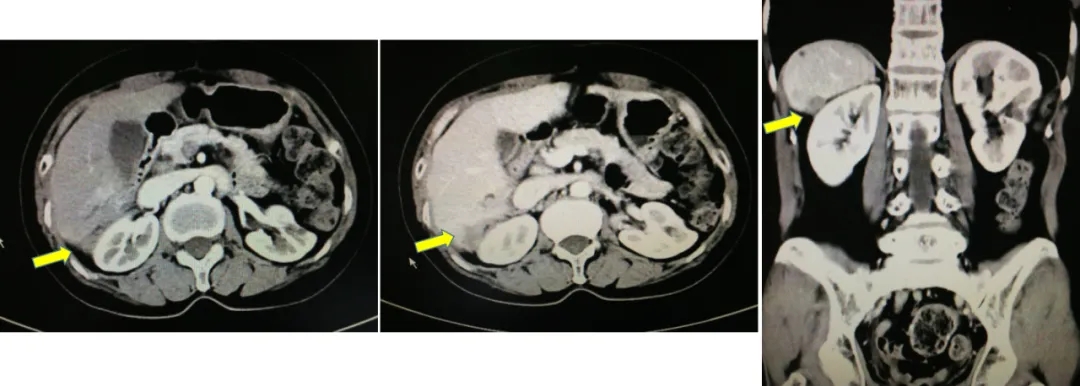

2014.4.12患者的CA125上升至81u/ml,2014.6.5 CA125上升至141u/ml。

B超:肝脏右后叶近肾区局部片状回声欠均,左侧肾上腺区囊实性团。

2014.6.11 CT:脾周囊性低密度灶2.4*2.7cm,较2014.2.26增大,腹主动脉旁肿大淋巴结,考虑“卵巢癌复发”。

CT检查结果